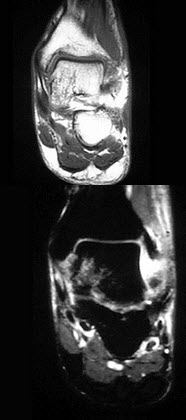

男,30岁,踝关节有内翻外伤史,结合图像,最可能诊断是()